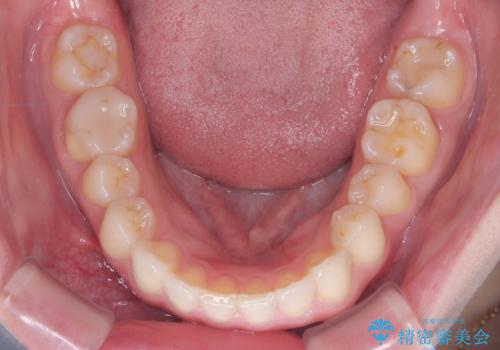

- 患者様は、上下顎の歯列不正と前歯部の突出感を主訴としてご来院されました。診断の結果、上顎左右第一小臼歯を抜歯することでスペースを確保し、歯列全体を整える方針としました。本来はワイヤー矯正が推奨されるケースですが、患者様のご希望により、透明なマウスピース型矯正装置「インビザライン」を使用した治療計画を立案しました。治療期間は約3年で、奥歯の噛み合わせを維持しながら、徐々に前歯の位置を整えました。

インビザラインは見た目の目立ちにくさと取り外しが可能な点がメリットですが、複雑なケースでは治療計画の精密さが求められます。本症例では奥歯の噛み合わせが崩れないよう注意を払いながら、マウスピースの交換タイミングを細かく設定しました。患者様には装着時間を守っていただくことが重要で、1日20時間以上の装着が必須です。また、抜歯部位のスペースを閉じる過程で、歯の動きが停滞しやすい時期もあるため、定期的なチェックを通じて治療が順調に進むよう管理しました。